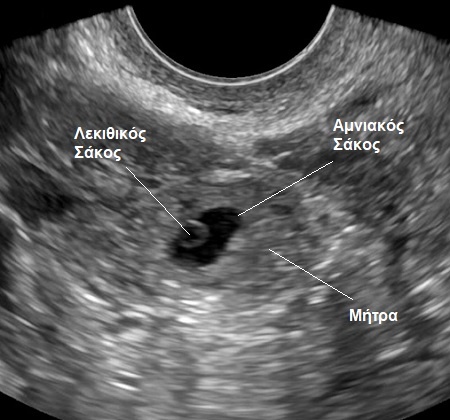

Η πρώτη ανατομική δομή του εμβρύου, που εντοπίζουμε υπό κανονικές συνθήκες εντός του αμνιακού σάκου είναι ο λεκιθικός σάκος (ή «ασκός»).

Πρόκειται για ένα μικρό σφαιρικό όργανο, το οποίο στο υπερηχογράφημα απεικονίζεται ως ένας μικρός κύκλος μέσα σε έναν μεγαλύτερο κύκλο, που είναι ο αμνιακός σάκος (βλ. εικόνα).